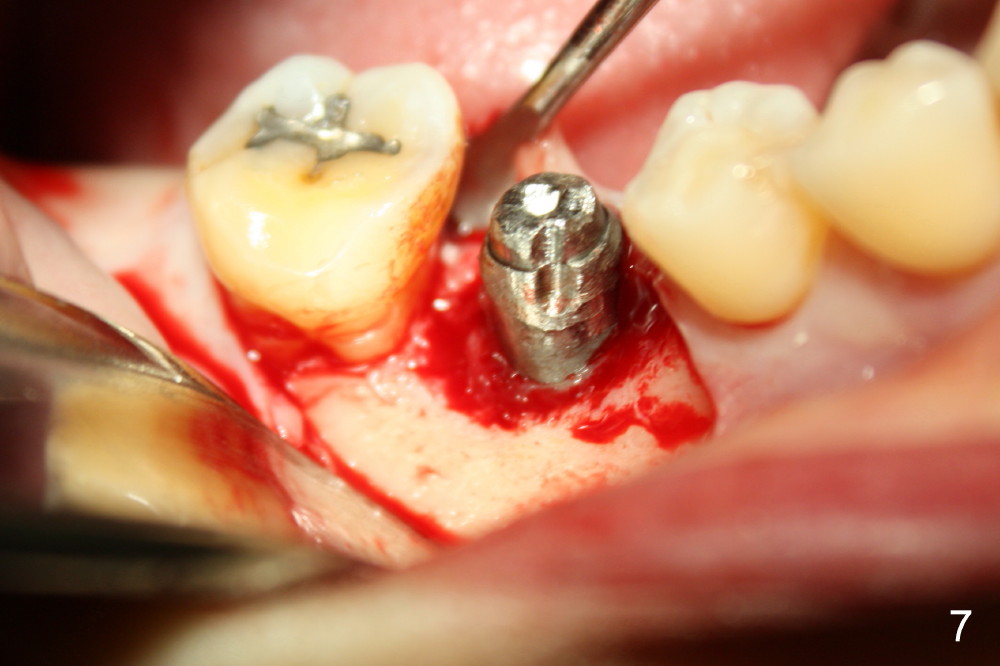

The infection may be related to chronic infection at the tooth #9. The latter is extracted, but the infection at the site of #30 does not resolve (Fig.5,6). The buccal flap is raised to reveal granulation tissue distobuccal to the implant (Fig.7). Bony defect and implant thread exposure are shown after debridement (Fig.8). Irradiated cancellous bone graft is placed to the defect (Fig. 9, Rocky Mountain Tissue Bank). The flap is closed with relative tension free. The definitive crown is temporarily cemented. The graft is exposed with no infection 2 week post grafting (Fig.10). The distobuccal defect appears to have healed 5 months post grafting (Fig.11) and the crown is permanently cemented (Fig.12). There is no buccal bone resorption, probably associated with immediate implantation. The patient remains asymptomatic 13 months postop.